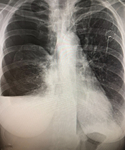

Anterior-posterior chest x-ray demonstrating a right pneumothorax

From the collection of Dr Ryland P. Byrd